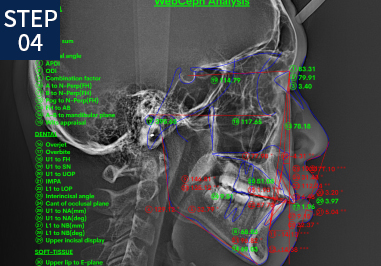

걸포탑치과는 서울대 출신 교정과 전문의가 치아교정을 진행합니다. 단순 치아 상태가 아닌 잇몸뼈, 턱뼈, 턱관절, 혀 위치 등을 확인하여 통합적인 기준으로 치료계획을 세워드립니다.

• X-RAY/구강/안면촬영

• 분석 및 치료계획 수립